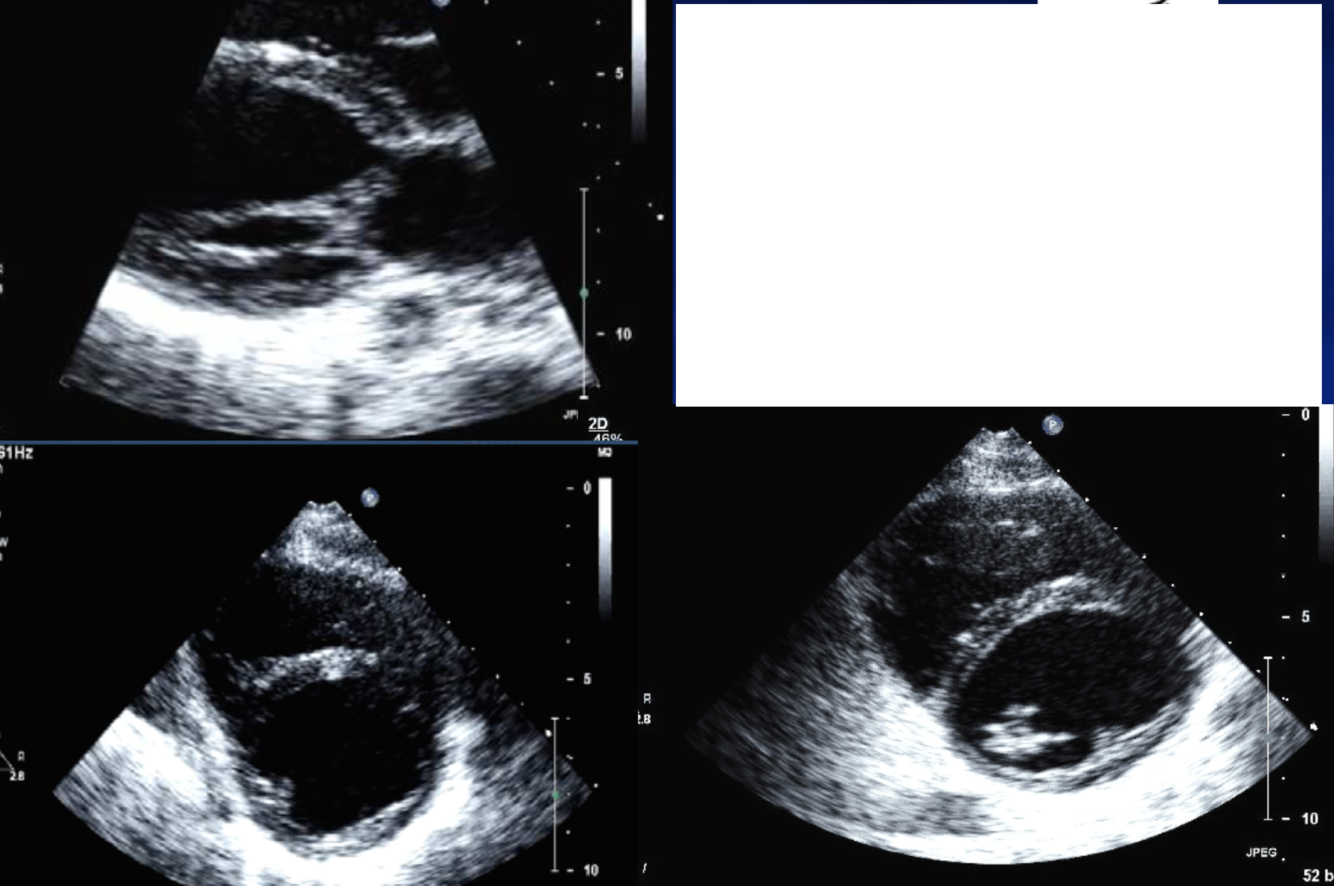

Diagnosis

Parachute MS

Medication Induced MS (small/retracted leaflets with thick tips

MVP

SAM